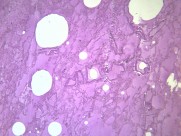

肺水肿(pulmonaryedema)是肺脏内血管与组织之间液体交换功能紊乱所致的肺含水量增加本病可严重影响呼吸功能,是临床上较常见的急性呼吸衰竭的病因。主要临床表现为极度呼吸困难,端坐呼吸,紫绀,大汗淋漓,阵发性咳嗽伴大量白色或粉红色泡沫痰,双肺布满对称性湿啰音,X线胸片可见两肺蝶形片状模糊阴影,晚期可出现休克甚至死亡。动脉血气分析早期可有低O2、低CO2分压、严重缺O2、CO2 潴留及混合性酸中毒。